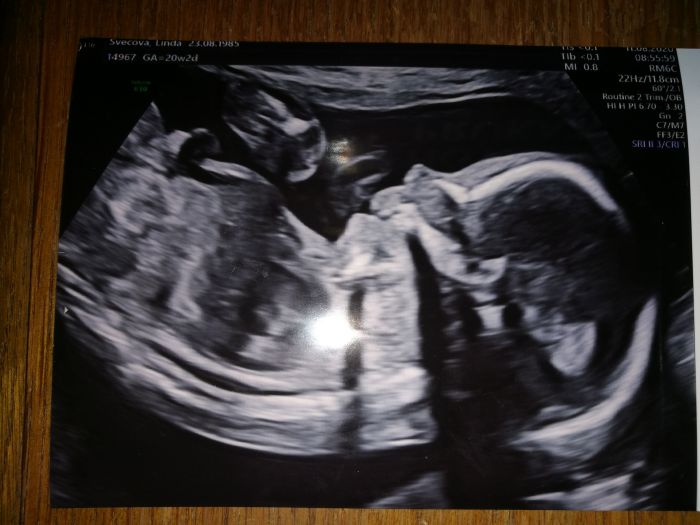

Tak mám po screeningu. Vše je vpořádku, placenta sice nízko ale prý se zvedne. Ani nevím co to znamená pro mě kdyby byla nízko.. Malá se pořád mlela :) Bude to další živé dítko :) posilam

Autor: Pampelis 11.8.2020 v 16:43

to 3D nakonec neudělali.. byla tam jiná sestra než minule a tato mi to ani neukázala. Ta předtím ano a říkala že příště by šla fotka udělat. No. tak se mám prý na 3D objednat 25 týden tak uvidíme